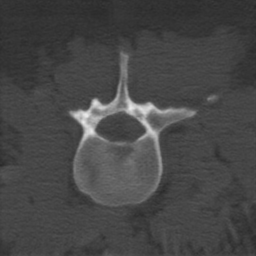

CBCT data. The CBCT data were collected by a Siemens Arcadis Orbic 3D system during spinal intervention. The dataset contains 109 CBCT scans and all of the scans cover two or three lumbar vertebrae. The size of CBCT volumes is 256 256 256. The isotropic voxel size is 0.5 mm. Due to the severe cone-beam geometry distortion at the two ends of the sagittal axis, we only keep 196 slices in the middle for each volume. We use 97 volumes for training and 12 volumes for testing, resulting in 19,012 slices in the training set and 2,352 slices in the testing set. To evaluate the segmentation performance, the vertebra masks for the testing set only were manually labeled by an expert.

Disentanglement and explicit shape constraints. As shown in Fig. 4, we can see streak metal artifacts nearly everywhere in . M1 can roughly disentangle artifacts and anatomical information but strong vertical artifacts and strange air area appear in (see red arrows of M1 in Fig. 4). For the anatomical structure, M1 learns to segment vertebrae with fully supervised and applied on various CT images, but fails to suppress the false bony structure in and as may misclassify some metal artifacts as bone.

Implicit shape constraints. With , all segmentations are improved with higher Dices and smaller ASDs, see Table 1. As shown in Fig. 4, , and become similar but the high density bone is not correctly segmented in as it maybe treated as metal artifacts. Comparing between M2 and M1, the abnormal air region disappears but metal artifact reduction performance is still not satisfactory.

Anatomy-aware generation. With AADE layer in M3, , and are substantially improved as shown in Table 1. Note, is used as attention map, so we do not expect it to be identical to . In , metal artifacts are further suppressed comparing with M2. Thus, AADE is critical to our anatomy-aware artifact disentanglement framework. With the special structure, can be punished in the image translation and reconstruction processes and the other encoders and generators receive more guidance. However, as shown by blue arrows in Fig. 4, we observe a shadow of vertebra edge of appears in of M3 and the vertebra boundaries get smoothed out in . It may be because sharp edges are encoded as metal artifacts and forced to be added to by artifact consistency loss .

Removal of . To mitigate vertebrae shadows, we remove . The segmentation performance of most images in M4 gets improved because of better synthetic images. Overall, in M4 yields the best segmentation performance for CBCT images with an average Dice of 0.847 and an average ASD of 1.54 mm. For the synthetic images, M4 generates with the best quality and least metal artifacts among all the models. M4 also outputs without vertebra shadows. The results indicate our shape-aware network could preserve anatomical details and transfer the metal artifacts precisely without .